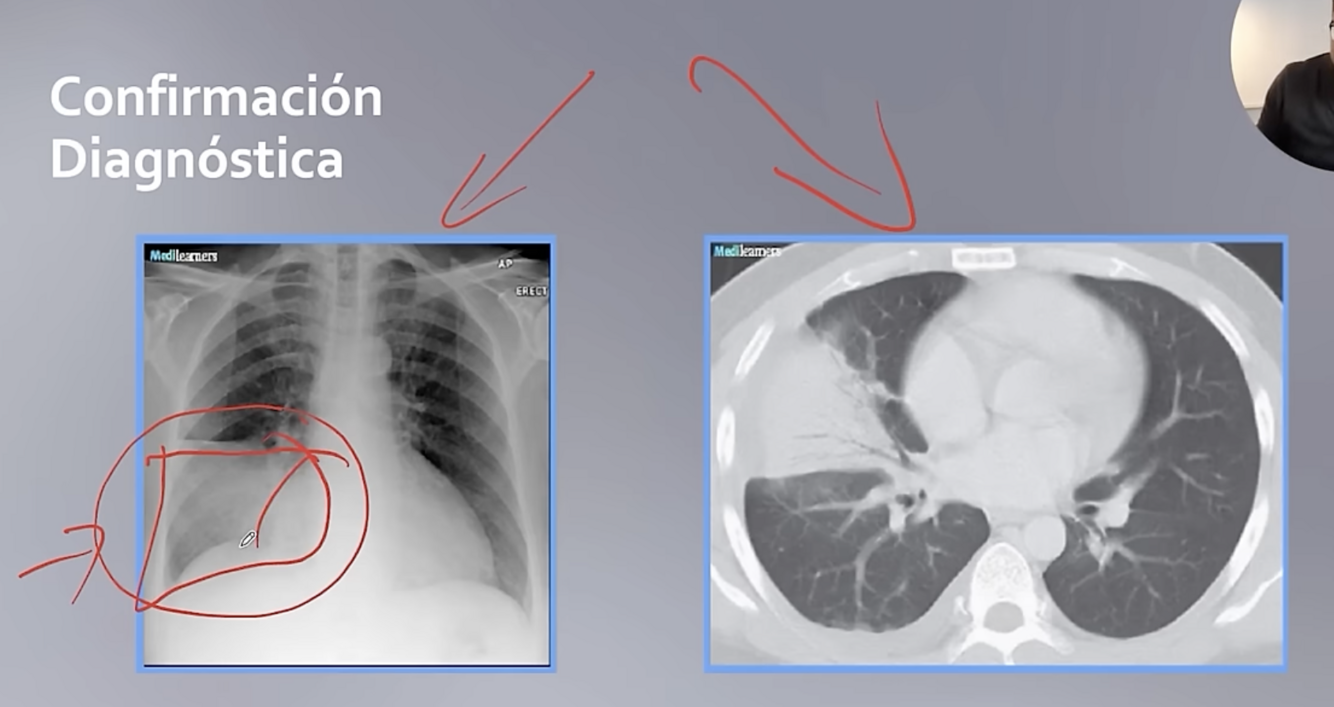

Q

Como confirmo el dx d

A

Con un estudio de imagen